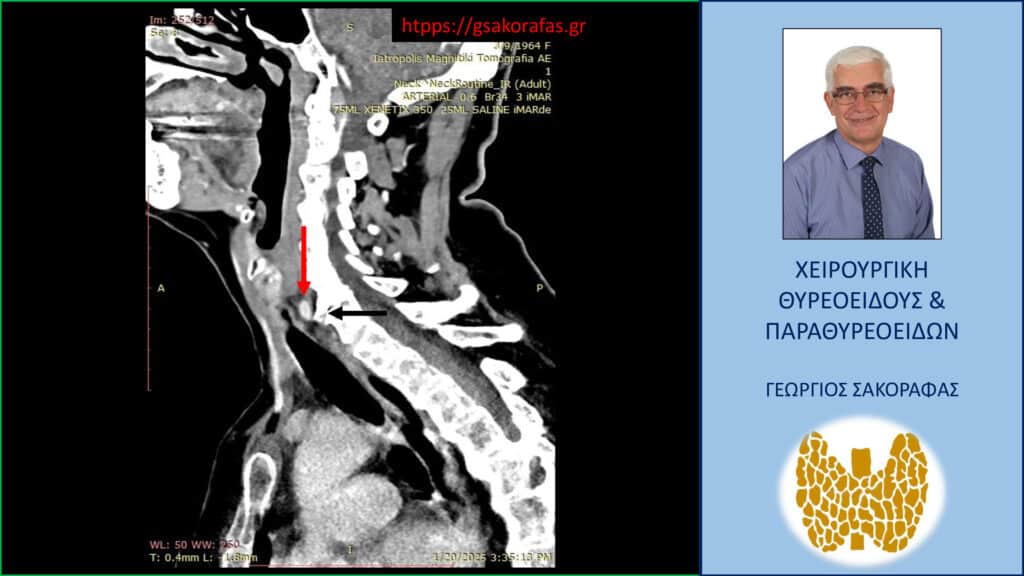

- Γιατί είμαστε σε θέση να εκτελέσουμε με ασφάλεια και αποτελεσματικότητα κάθε είδους χειρουργική επέμβαση θυρεοειδούς – παραθυρεοειδών, ακόμη και σε επιπλεγμένα (δύσκολα) περιστατικά, όπως εκτεταμένοι λεμφαδενικοί καθαρισμοί σε καρκίνο θυρεοειδούς, επεμβάσεις σε λίαν ευμεγέθεις καταδυόμενες στο μεσοθωράκιο βρογχοκήλες, υποτροπές παθήσεων θυρεοειδούς (συμπεριλαμβανομένου του καρκίνου θυρεοειδούς), υποτροπές υπερπαραθυρεοειδισμού, αδενώματα παραθυρεοειδών σε έκτοπη θέση ή λόγω υπεράριθμων παραθυρεοειδών, διάχυτη υπερπλασία παραθυρεοειδών, κλπ.